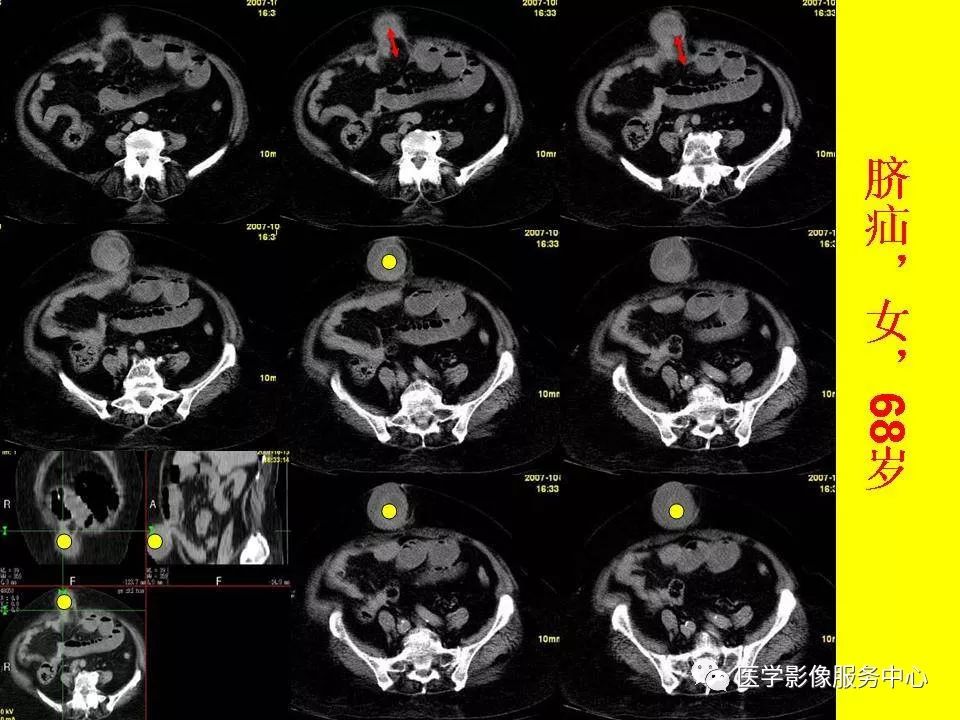

女性老年患者肠梗阻元凶之闭孔疝